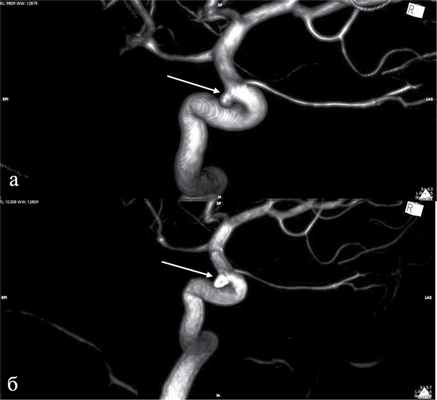

Рис. 2. 3D-Ангиограммы пациентки с аневризмой офтальмического сегмента левой внутренней сонной артерии. а — исходные ангиограммы (аневризма указана стрелкой); б — после тотальной окклюзии аневризмы микроспиралями (стрелка).